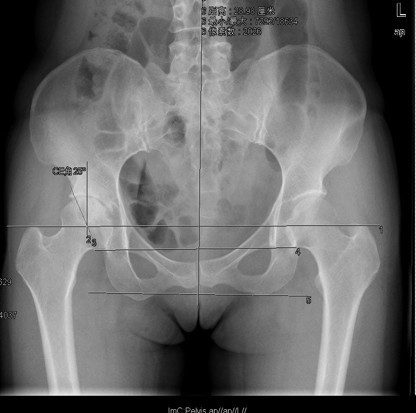

查体:右髋部软组织未见肿胀,双下肢皮肤无破溃,双足趾间皮肤干燥、完好。右髋部后侧轻压痛,双侧足背动脉和胫后动脉搏动正常。 辅查:X线:双侧侧髋臼较浅,髋臼外上方软骨下骨硬化及骨赘,Sharp角右侧约48°、左侧约50°,CE角右侧约20°、左侧约18°,右侧髋关节间隙狭窄,右侧髋臼、股骨头可见囊性改变。

诊断: 1.右侧髋关节发育不良骨关节炎(crowe I型) 2.左侧髋关节发育不良(crowe I型) 3.上呼吸道感染 治疗:排除手术禁忌症后择期手术治疗。